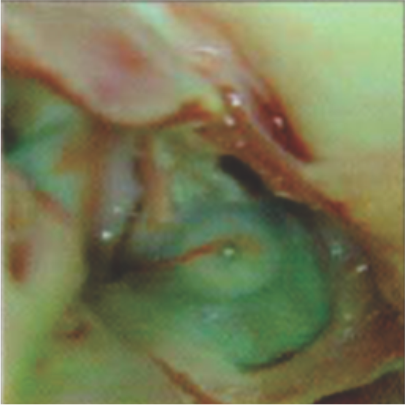

Neoendothelialization on the left atrial surface of the device at 36 days after implantation

Neoendothelialization on the left atrial surface of the device at 42 days after implantation

Neoendothelialization on the right atrial surface of the device at 36 days after implantation

Neoendothelialization on the right atrial surface of the device at 42 days after implantation